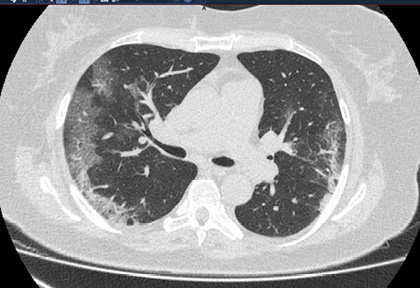

Routine clinical laboratory assays were performed in the hospital’s clinical laboratories. Clinical and laboratory information was extracted from the patients’ medical records. C reactive protein (CRP) in plasma was measured by immunoturbidimetry (Beckman Coulter, Krefeld, Germany). Interleukin-6 (IL-6) levels in plasma were measured by electrochemiluminescence (Siemens Medical Solutions Diagnostics, Siemens Healthcare, Erlangen, Germany). CT scans were read by experienced radiologists who scored results by severity using the criteria shown in Figure 1.

Figure 1. Clinical assessment of pneumonia severity based on computed tomography (CT) scores.

Scoring method: Mild (CT-1)—no more than three ground-glass opacities of <3 cm maximum diameter. Moderate (CT-2)—more than three ground-glass opacities; less than 50% involvement by visual assessment. Medium-heavy (CT-3)—ground-glass opacities and pulmonary consolidation; 50-70% involvement by visual assessment. Severe (CT-4)—diffuse ground-glass opacities with or without consolidation; more than 75% involvement by visual assessment.